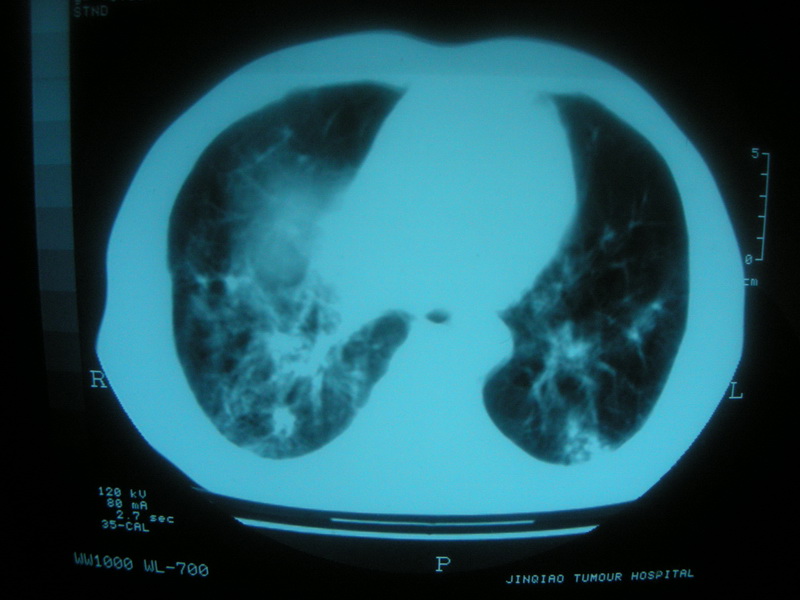

标题: CT11692:男,63岁,糖尿病史15年.抗炎治疗7天,病情 [打印本页]

标题: CT11692:男,63岁,糖尿病史15年.抗炎治疗7天,病情

请老师看看是结核还是炎症?

根据影像表现及临床符合结核感染。

双肺继发性肺结核伴感染!

双肺继发性肺结核伴支气管播散。

糖尿病首先考虑结核并感染。